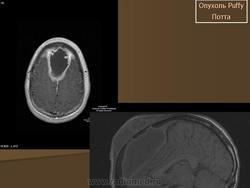

Описанная впервые сэром Персивалем Поттом в 1760 году, "одутловатая" опухоль представляет собой тестообразное вздутие на лбу, вызванное эрозией передней стенки пазухи, как последствие остеомиелита лобной пазухи. Инфекционное воспаление кости может произойти непосредственно или чаще всего из-за тромбофлебита диплоических вен, в результате которого происходит инфицирование костного мозга. Чаще всего в процесс вовлекается лобная кость. Осложнения, как правило, наблюдаются у подростков и молодых людей, возможно, в связи с тем, что у них диплоические вены наиболее развиты. Основной возбудитель инфекции - Staphyloccocus aureus. Радиография выявляет участок кости, будто выеденный молью. На ранней стадии болезни, однако, результаты рентгенографии или компьютерной томографии бывают нормальными.

7. Опухоль Потта представляет собой субпериостальный абсцесс лобной кости. Является осложнением воспалительного процесса в лобной пазухе. Часто сочетается с развитием эпидурального абсцесса. Лечение хирургическое - санация лобной пазухи наружным, реже - внутриносовым доступом с удалением кариозно измененной кости в сочетании с антибиотикотерапией.